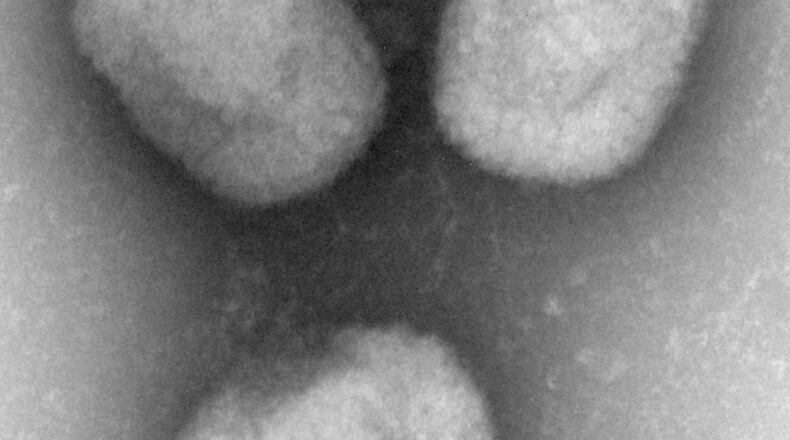

Monkeypox is a rare viral pox-like disease from the smallpox family, only milder. It can be transmitted through respiratory droplets, contact with body fluids or contact with an infected animal or animal products.

Monkeypox symptoms typically begin with flu-like illness and swelling of the lymph nodes, then a widespread rash on the face and body, according to the CDC. Most infections last two to four weeks. Infections with this strain of monkeypox are fatal in about 1 in 100 people, but the mortality rate can be higher among those with weakened immune systems.